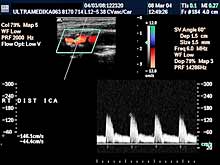

A) Krvni sudovi vrata

Vrsta i sadržaj pregleda:

- Pregled velikih krvnih sudova vrata CD i CPA

modom (obavezno karotidnih i vertebralnih arterija celim tokom).

Pregled podrazumeva procenu ukupne debljine krvnih sudova (indirektna

procena koronarne bolesti), procenu stepena suženja, karakteristika aterosklerotičnog plaka, procena hemodinamike i postavljanje

indikacija za operativno lečenje.

Primenjena tehnika:

- Sono CT,

- XRes,

- 2D Broad band,

- Broad band - CD,

- CPA ,

- CPD.

Preporučeni pregledi:

- nakon 45. godine starosti,

- obavezno ako postoje

faktori rizika

(hipertenzija, pušenje, stres, poremećaj nivoa masti u

krvi, kod sumnje da postoji koronarna bolest),

- kontrola na 6-12

meseci.